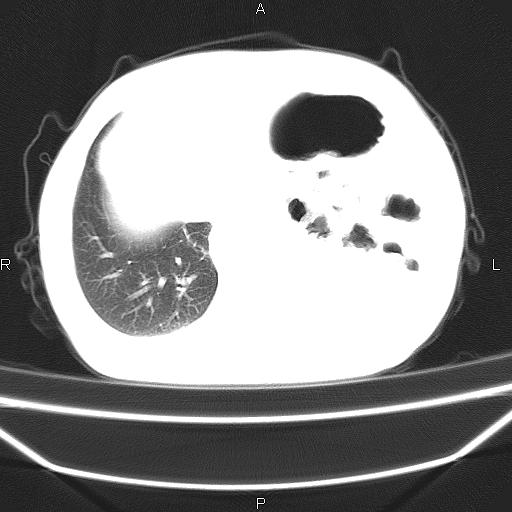

患者,男。50岁。近几日有咳嗽症状,无其他不适,既往病史无,考虑膈疝。请前辈们看看指导指导。

膈膨升,左下肺通气不良,膈肌好像还完整。

考虑左侧膈疝。

左侧膈疝。

符合隔膨升,膈肌较完整。